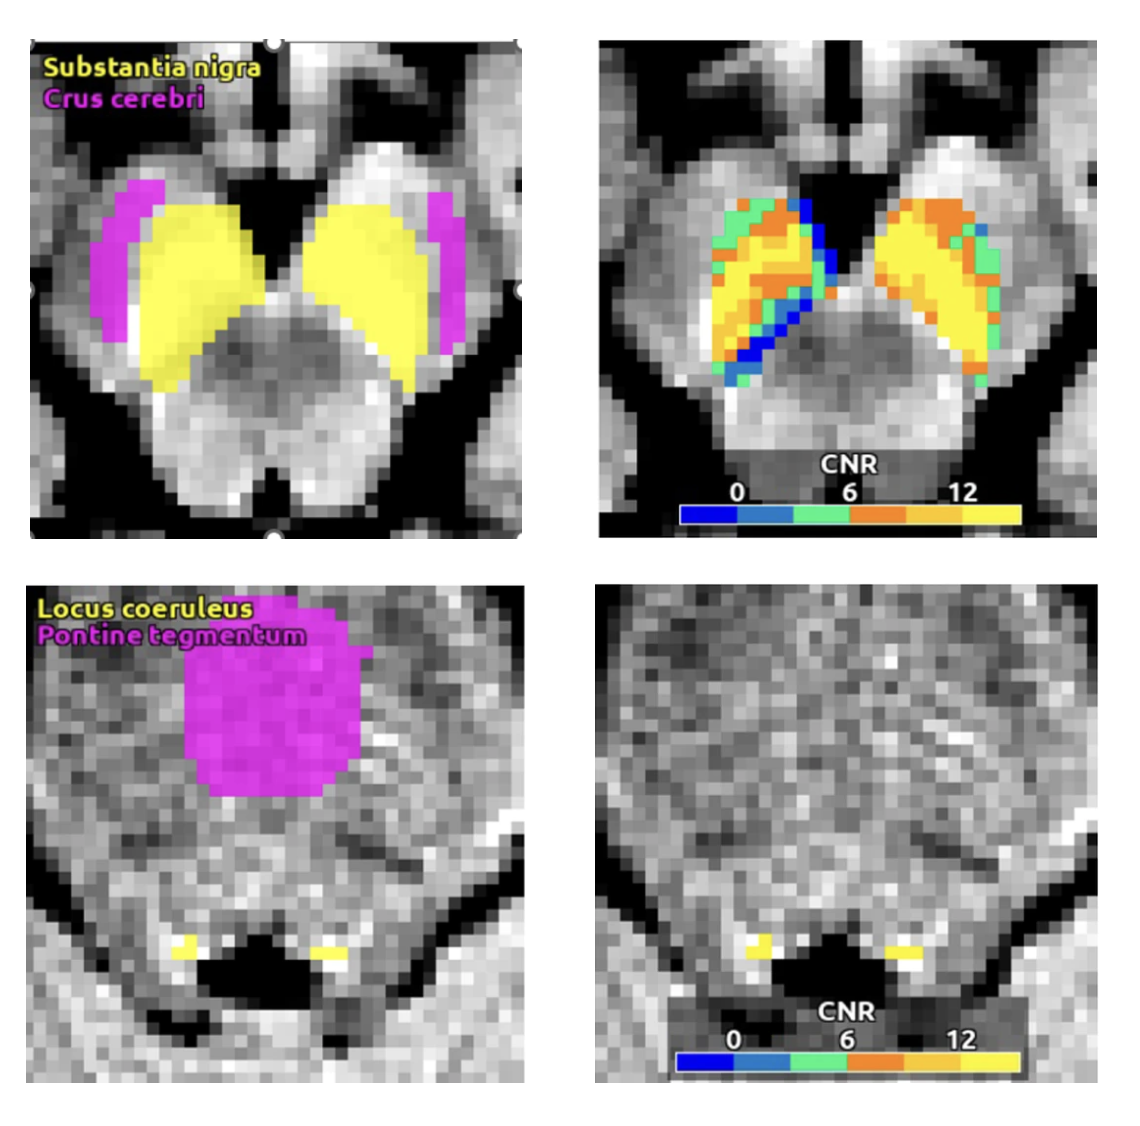

Despite these benefits, there have been no FDA-approved devices capable of providing clinicians with analysis of neuromelanin MRI due to a lack of automation and standardization that has prevented its clinical use. Historically, the standardization of neuromelanin measurement has been difficult due to variability in results among MRI scanners, even those from the same manufacturer and model [7,8]. NM-101 contains algorithms that enabled for the first time the fully automated analysis and the cross-scanner harmonization of neuromelanin MRI scans [8-10,12,13].

Guillermo Horga, MD, PhD, Associate Professor of Psychiatry at Columbia University Vagelos College of Physicians and Surgeons, and Clifford Cassidy, PhD, now Assistant Professor of Cellular and Molecular Medicine at the University of Ottawa, were pioneers of the original algorithms and authors of studies using neuromelanin MRI in neuropsychiatric disorders including schizophrenia [9,12].

“Now that we’re able to access measurements of neuromelanin-associated signal in both the substantia nigra and locus coeruleus,” added Dr. Cassidy, “it allows us to obtain potentially useful adjunctive information about many other diseases such as Alzheimer’s disease, and PTSD.”